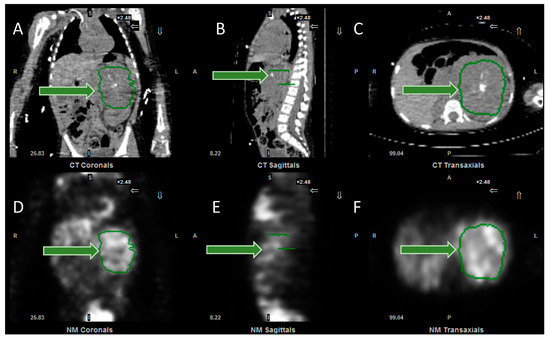

Selective Internal Radiotherapy (SIRT) is a treatment using radiolabelled microspheres to treat liver tumours with indications including hepatocellular carcinoma (HCC) and liver metastases from colorectal cancer (mCRC) [36]. Benefits have been seen for the treatment of liver metastases for some other primary cancers as well [37]. Radiobiologically guided dosing strategies are possible [38]. Patients undergo a hepatic angiogram to perform embolisation to prevent shunting to extrahepatic areas and to administer 99mTc-MAA (macroaggregated albumin) for imaging prior to treatment. The treatment consists of 90Y-microspheres, which are delivered through the same hepatic route to deliver the dose directly to the tumours. The 90Y-microspheres remain in situ, permanently irradiating the tumour sites until the radioactivity physically decays away. The work up imaging allows dose calculation for personalised treatment and allows the identification of shunting. There are two types of 90Y-microspheres: resin spheres at 20–60 µm diameter and glass spheres 20–30 µm. 90Y is a predominantly beta-emitting radioisotope, so imaging can be challenging. Bremsstrahlung imaging or PET imaging is required to image post therapy. A workup with 99mTc-MAA and PET imaging of the 90Y-microspheres is shown in Figure 3.

Figure 3.

Selective internal radiotherapy with radiolabelled microspheres for liver metastases. (A) Axial and (B) coronal fused SPECT CT images of 99mTc-MAA (macroaggregated albumin) pre-treatment imaging for dose calculation and treatment verification. Corresponding (C) axial and (D) coronal post-therapy PET CT images following therapy with 90Y-microspheres.

166Ho–microspheres are a newer product on the market, which are a gamma-emitters and have paramagnetic properties allowing for SPECT and MR imaging. The product also has the option of low-dose 166Ho-microspheres are for the workup to more accurately mimic the treatment, as they use the microspheres themselves for the pre-therapy imaging. [39]